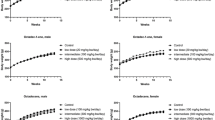

There was no significant treatment-related effects on the survival rate (Fig. 1, Table 1). Emaciated (39 in males; 35 in females) or crouching position (22 in males; 9 in females) were observed at infrequent intervals for males and females exposed to 300/200 ppm. All other signs observed in this study were of the types normally encountered in B6C3F1 at this laboratory and occurred at the expected frequencies. The body weights of both sexes in the 300/200 ppm groups were significantly decreased throughout the study compared to those of the control (Fig. 2). The water and food consumptions of both sexes administered 300/200 ppm were significantly lowered throughout the study than those of the control (Fig. 3). Concentrations of 30, 100 or 300/200 ppm 3-MCPD in the drinking water resulted in average daily consumptions of approximately 4.2, 14.3, and 33.0 mg/kg 3-MCPD for males and 3.7, 12.2 and 31.0 mg/kg 3-MCPD for females, respectively. The formulations investigated during the study were found to comprise 3-MCPD within the range of 98.52–107.0% of nominal indicating satisfactory preparation of the dose formulations.

The suppression of body weights at 300/200 ppm in both genders during the experiment is associated with sweetish taste of 3-MCPD and is consistent with previous 13-week B3C3F1 mice and 104-week SD rat study reported by us (Cho et al. 2008a; Cho et al. 2008b), and the results of the 2-year carcinogenicity study with F344 rats (Lynch et al. 1998) as well. Food and water consumption was decreased at 300/200 ppm groups for both sexes. A number of other differences in hematology (platelets, MCH, RDW and monocytes) and serum biochemistry (BUN, ALP and triglyceride) when compared to controls showed statistical significance. However, these variances were not consistent with the histopathological evidences and were not considered of great biological importance.